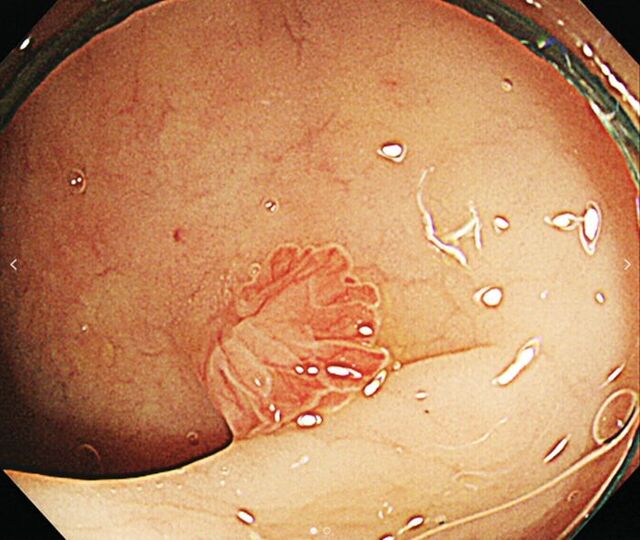

서울대병원 영상의학과 이동헌 교수팀이 약 3400건의 대장 내시경 영상을 학습·검증한 AI 대장 내시경 시스템(ColonOOD)을 개발하는 데 성공했다.

연구팀이 개발한 새 AI 대장 내시경 시스템은 용종의 위치와 유형을 자동 분류한다. 우선 고위험 용종을 1차적으로 구분하고, 그 밖의 유형일 경우 추가 분석 모델이 작동돼 저위험 과형성 용종과 소수 유형 용종을 감별한다. 용종 분류 시 기존 모델에선 제공되지 않았던 분류 결과의 신뢰 수준(높고 낮음)을 함께 제시함으로써 내시경 전문의의 정확한 판단을 지원한다.

용종은 대장암 위험이 높은 ‘선종성’과 위험도가 낮은 ‘과형성 용종’으로 구분된다. 소수 용종은 이 두 가지 유형에 해당되지 않고 적은 빈도로 발생한다. 하지만 대장암의 잠재적 위험이 상존하며, 종류는 전통적 톱니형 선종, 무경성 톱니상 용종 등이 있다.

연구팀은 “이 같은 분류 성능을 4개 대학병원의 데이터와 2개 공개 데이터셋 기반으로 검증한 결과 전체 용종을 최대 79.7% 정확도로 분류해 냈으며 소수 유형 용종은 최대 75.5%의 높은 확률로 찾아내는 것으로 나타났다”고 밝혔다.

한편, 이번 연구 결과는 국제 학술지(Expert Systems with Applications) 최신호에 발표됐다.